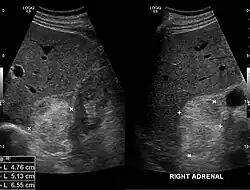

Myelolipom im Ultraschall.

Die Mehrzahl der Myelolipome sind asymptomatisch und werden zufällig, etwa im Rahmen radiologischer Untersuchungen oder einer Obduktion gefunden. Nur gelegentlich, insbesondere bei größeren Tumoren, berichten betroffene Patienten von Bauch- oder Flankenschmerz. Selten bestehen endokrine Störungen wie das Cushing-, Conn-Syndrom oder eine angeborene Nebennierenhyperplasie.[1]